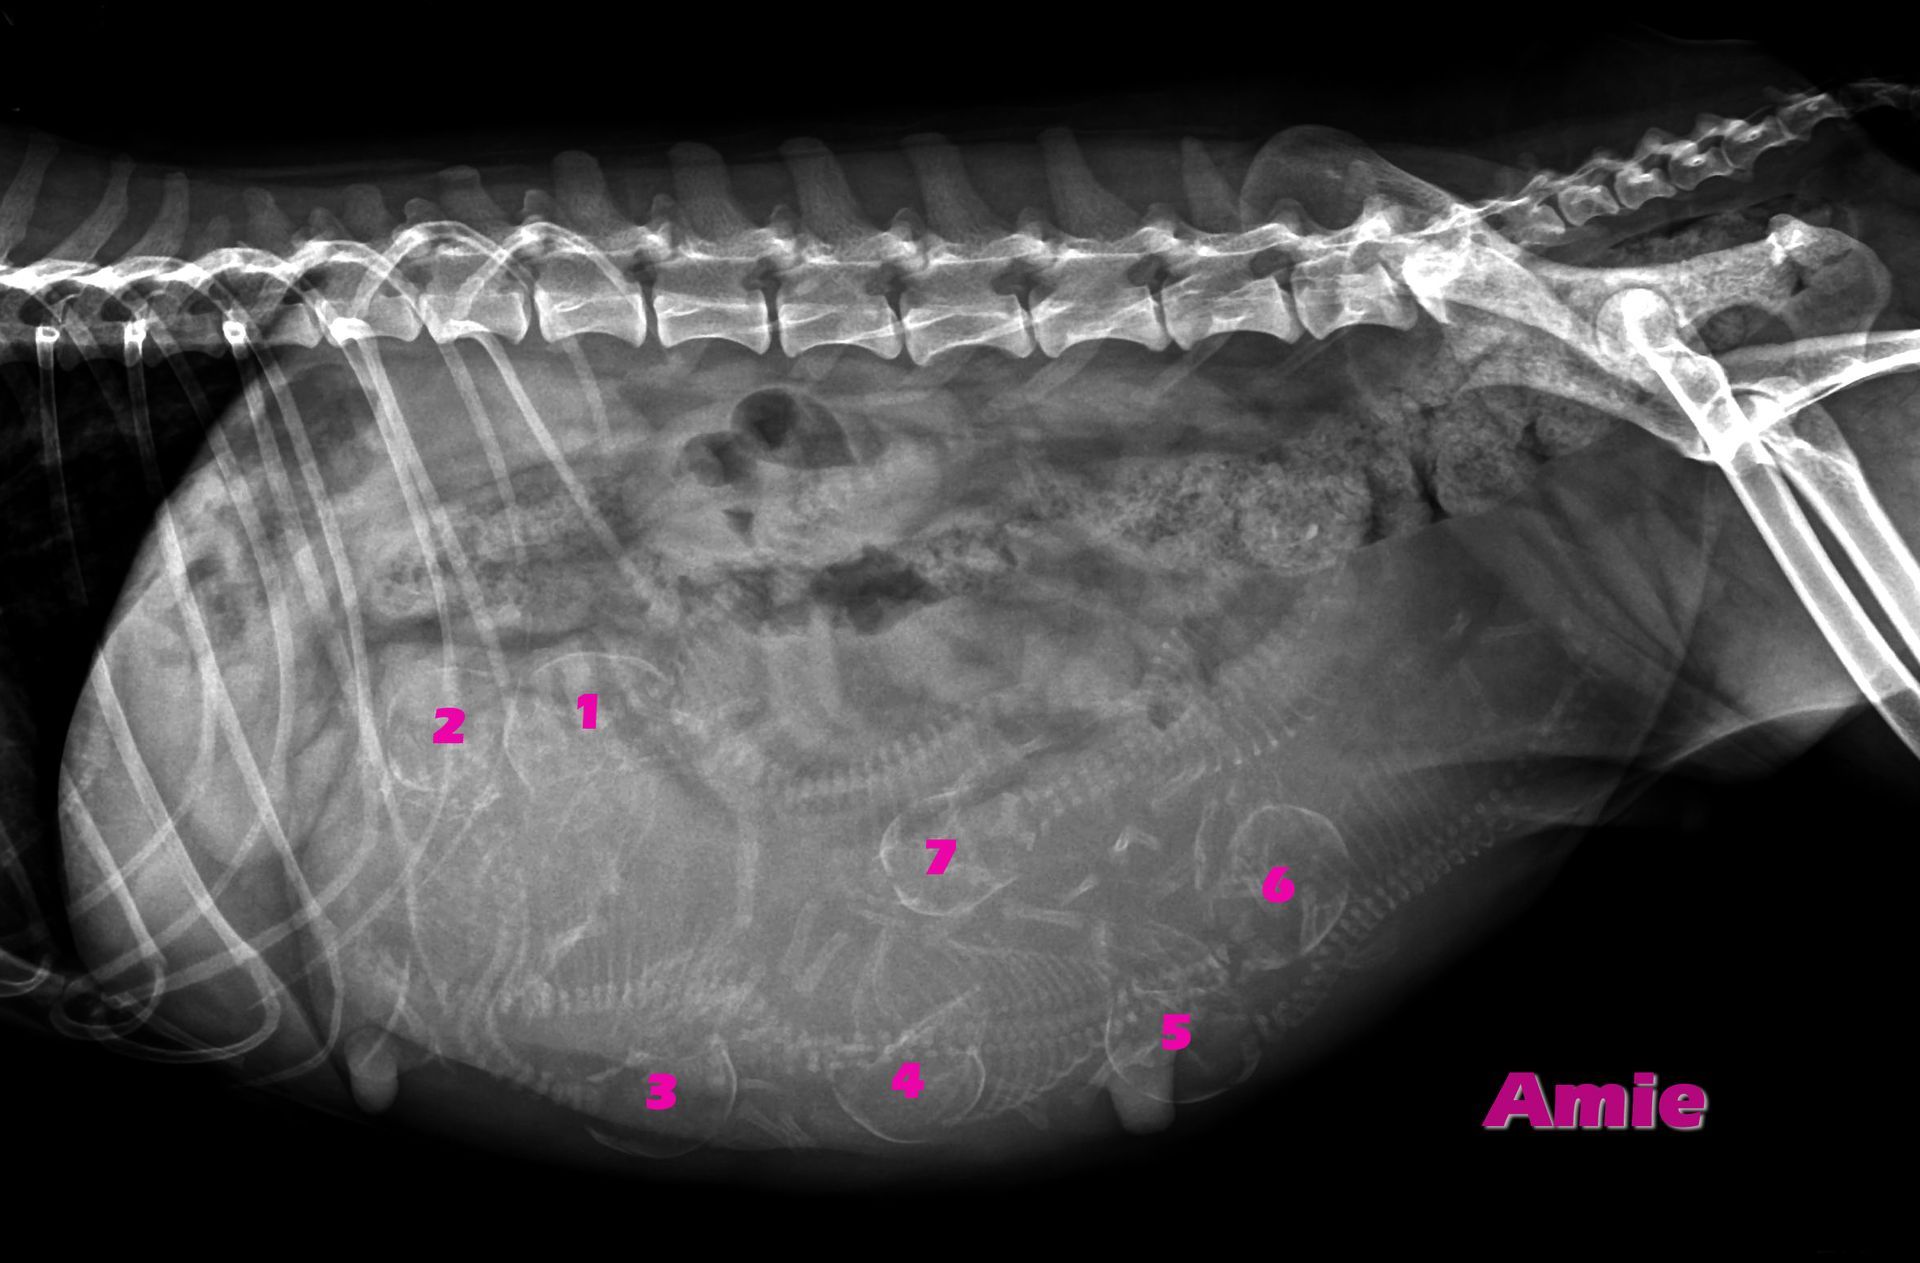

Amie hatte gestern ihren Röntgentermin

schaut einmal genau hin: seht ihr auch die sieben kleinen BabyBells, die Mama Amie in ihrem Bäuchlein versteckt hat? Ja, sieben kleine Fellnasen erwartet unsere liebe Amie. Da sind wir aber wirklich schon auf die Geburt gespannt...